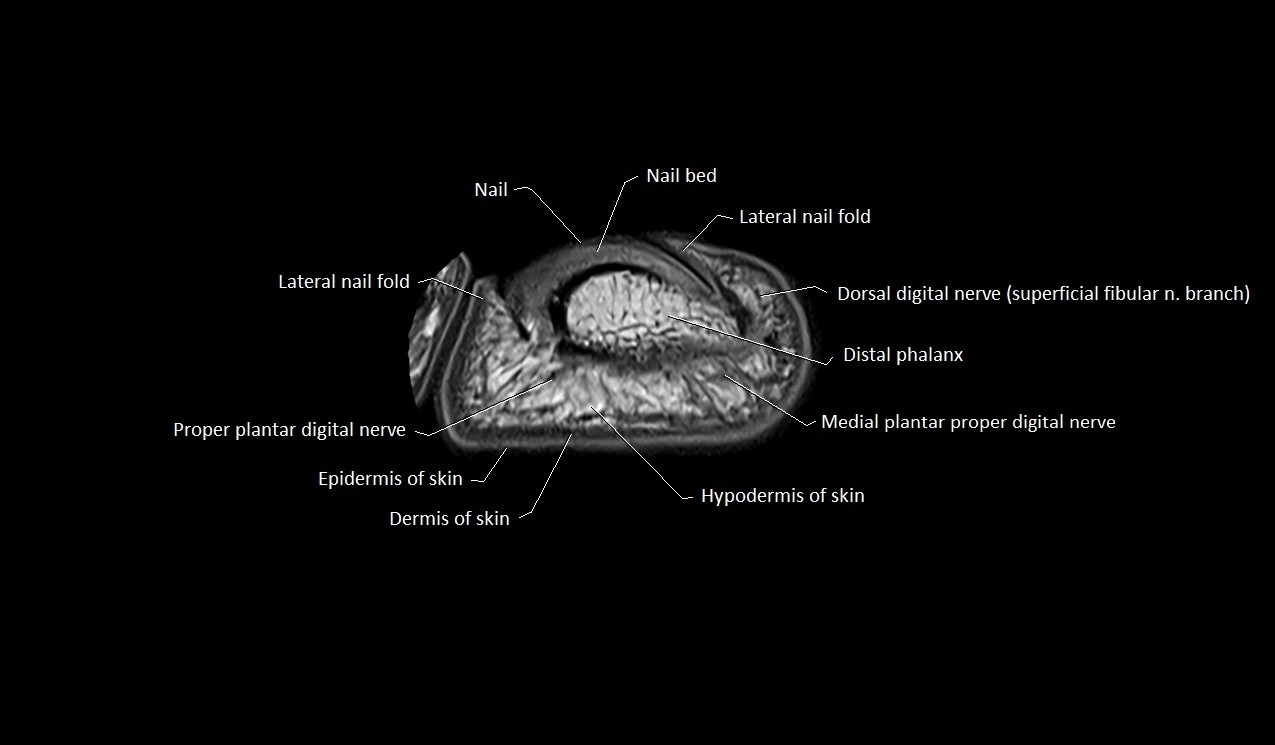

MRI image

image